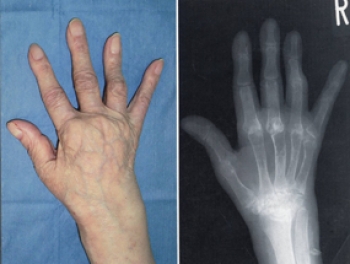

主に手足の関節を侵し、これにより関節痛、関節の変形もしくは破壊が現れます。

関節の変形や滑膜の細胞が増殖したり、軟骨の破壊が始まる。その後、関節も破壊し、関節は動かなくなってしまいます。

手の指の関節、第2関節(PIP)、第3関節(MP)が特に侵されます。また、手首や足の指、肘、膝など体の中心に近い大きな関節の痛みが出てくることもあります。

指の変形がひどくなると

スワンネック変形(白鳥の首状の変形)

ボタン穴変形

尺側偏位(指の全てが外側を向く変形   になります

レントゲン検査で典型的な関節所見

レントゲン